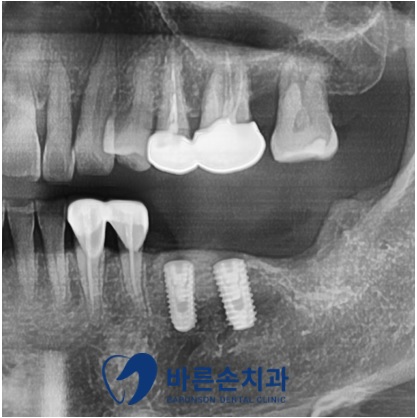

임플란트 식립 후 엑스레이를 통해

위치와 간격 모두 안정적으로 식립이 된 걸 확인할 수 있습니다

임플란트 식립 후 치조골과의 결합기간 2~3개월이 지난 후

크라운 제작을 진행함으로써

치료가 마무리되었습니다

양쪽 모두 어금니가 생겨 균형잡힌 식사를 하실수 있게 되었습니다.